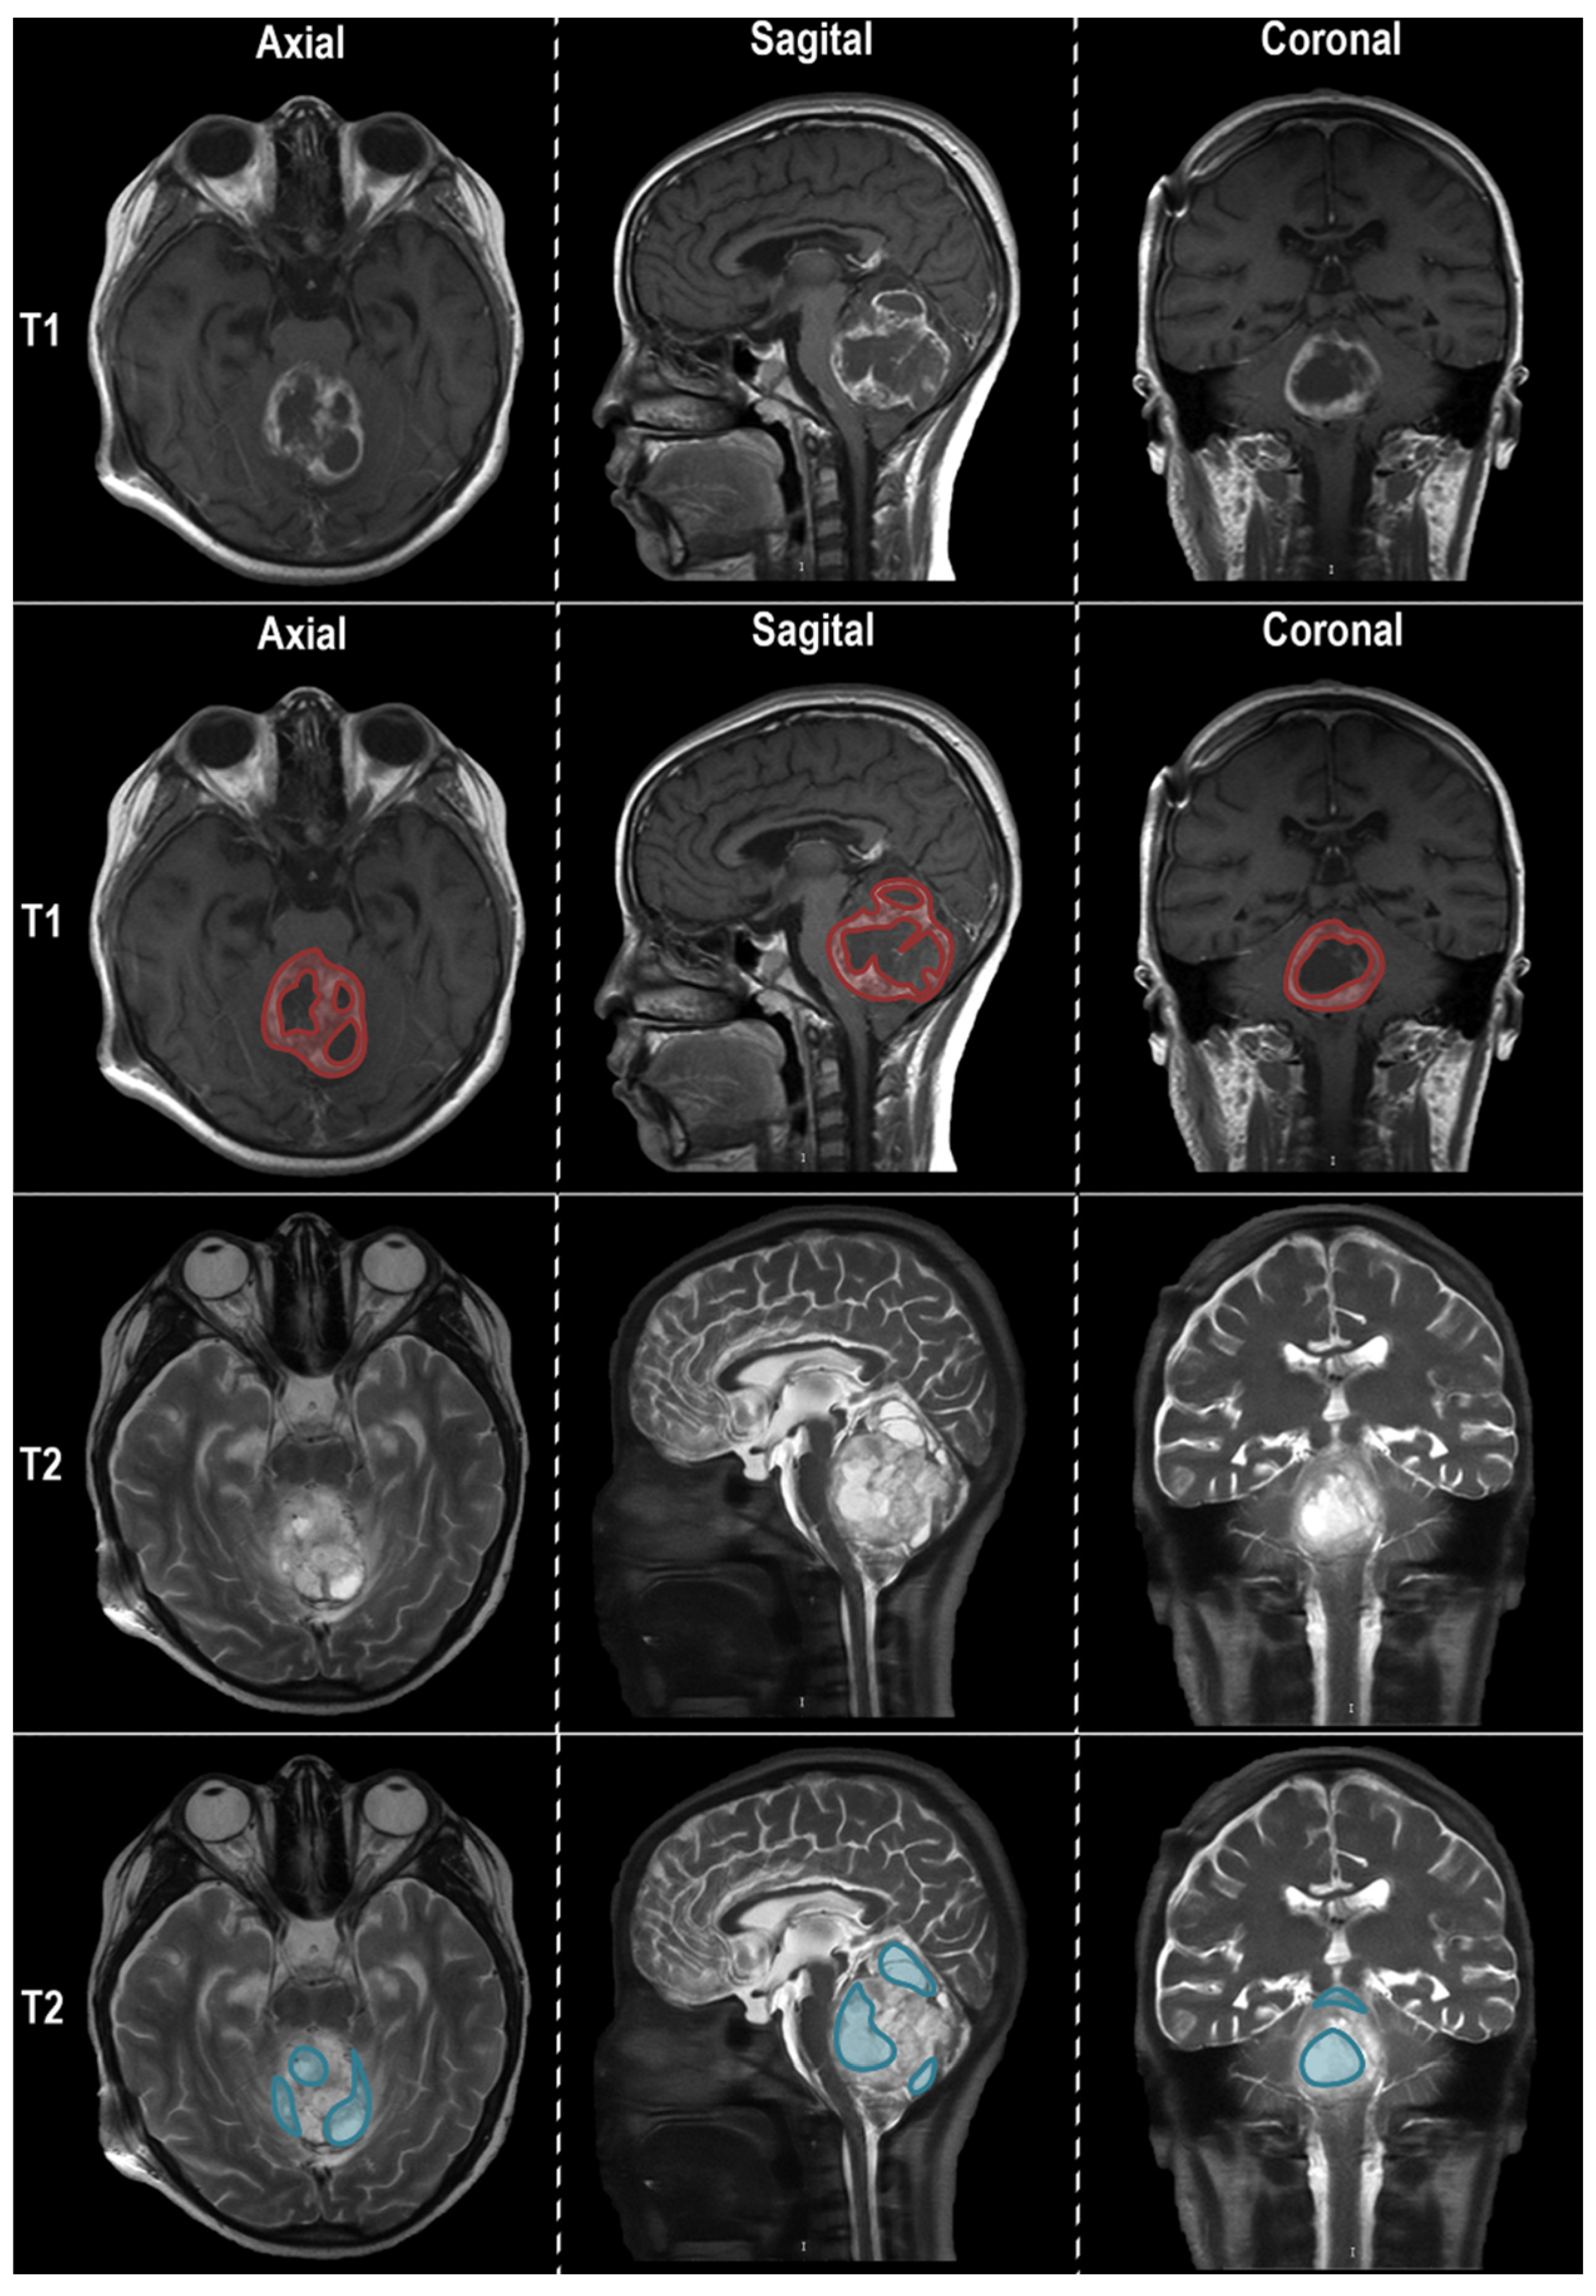

2.2. Imaging Evaluation of Midline Gliomas and Software for Calculation of Radiomics